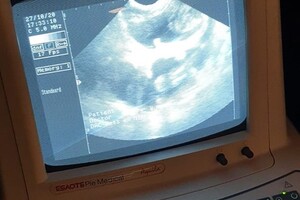

de dierenarts mocht Dakota eerst scheren, dit had ze nog niet eerder meegemaakt, maar ze vondt het niet zo erg, daarna heeft de dierenarts de scan gemaakt:

Ze is drachtig. het blijft moeilijk te zien hoeveel puppy's we kunnen verwachten, maar de dierenarts gaf aan dat we een mooi nest krijgen: niet te groot en niet te klein nest, ze ging uit van 4 a 5 puppy's. Dierenarts verwacht dan ook geen complicaties en een natuurlijke bevalling.